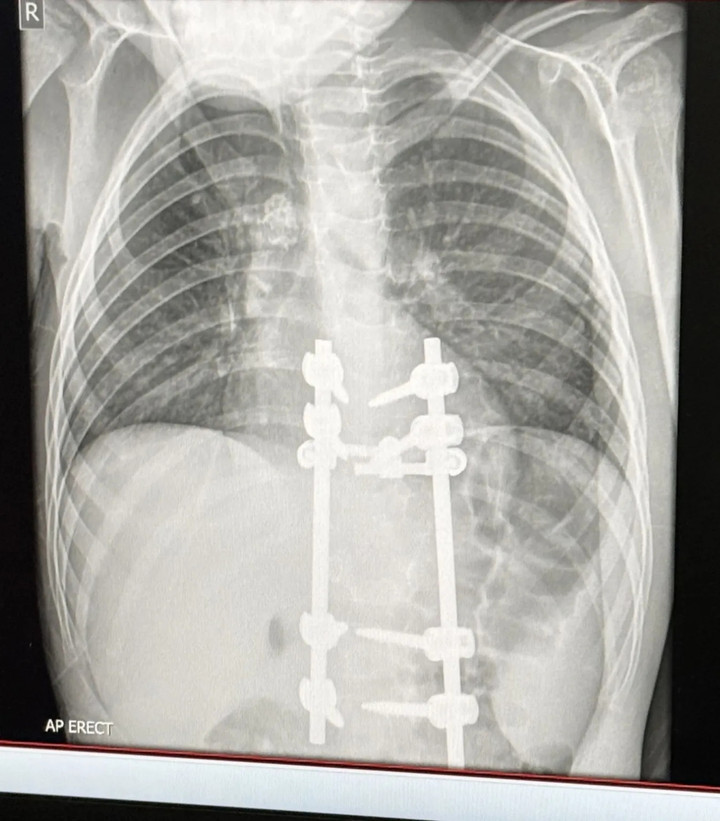

Kết quả X-quang của Elliot sau phẫu thuật. (Ảnh: Kennedy News)

Sau khi đánh giá kỹ lưỡng, các bác sĩ chỉ định phẫu thuật đối với cậu bé Elliot, nhằm giải phóng chèn ép ống thần kinh và ổn định lại cấu trúc cột sống.

Ca phẫu thuật đầu tiên đã thành công, Elliot hiện có thể đi bộ, nhưng chưa được phép chạy nhảy. Cậu bé sẽ đối mặt với lần phẫu thuật thứ hai trong vòng sáu tháng tới, nếu dấu hiệu tổn thương lao trên cột sống không thu nhỏ. Theo chia sẻ từ người mẹ, dáng đi của Elliot đã trở lại bình thường, các cơn đau dữ dội ở vùng lưng cũng biến mất.